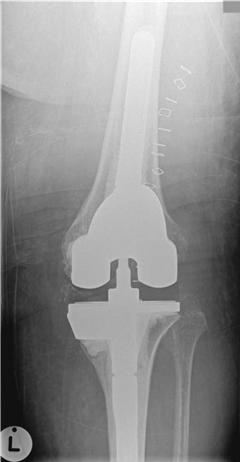

What implants do you use for revision total knee replacements?

What implant do you use for revision total knee replacements (TKRs)?

[ This question is aimed at exploring your understanding of pre-operative planning based on the individual requirements of the clinical case.] The range of implants or system I use would depend on the clinical situation: primary TKR, post stabilized, super-stabilized, rotating hinge, with stems ยฑ augments, tumour prosthesis. Whenever faced with a revision situation it is also prudent to consider both amputation and arthrodesis as options.

[You are passed a hinged prosthesis.] What are the benefi ts and disadvantages of this type of component?

These implants are used in ligament insuffi ciency and/or cases with major bone loss. The problems with increasingly constrained implants are transmission of high forces across the boneโcementโ implant interface which can lead to premature loosening.

If you where to revise a unicompartmental knee replacement what implant would you choose?

Ideally I would use a primary TKR implant. If there has been some tibial loosening and bone loss, a stemmed implant possibly with augments may be required.

If you had a patient with a posterior cruciate ligament (PCL) sacrifi cing knee with a complete medial collateral ligament disruption and dislocation what implant choice might you make?

Most likely I would require a rotating hinge stemmed system.